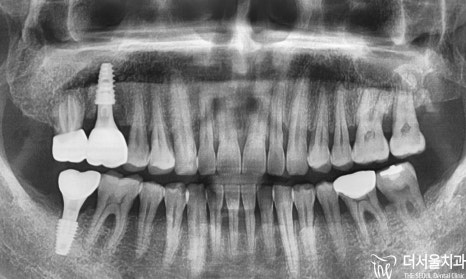

해당 우측 어금니쪽을 보았을때,

47번 어금니가 빠져있는 것을 볼 수 있으며,

17번 윗니는 아래로 내려온 것을

확인할 수 있었습니다.

정답은 옆에 있는 옆 어금니

16번에 나타난 잇몸 염증이죠.

실제로는 고름이 나올 정도로

염증이 심했었으며,

더는 사용할 수 없는 상태였기에

전체 진단은

# 16 : 발치 후 임플란트

# 17 : 신경치료 후 크라운

# 47 : 임플란트